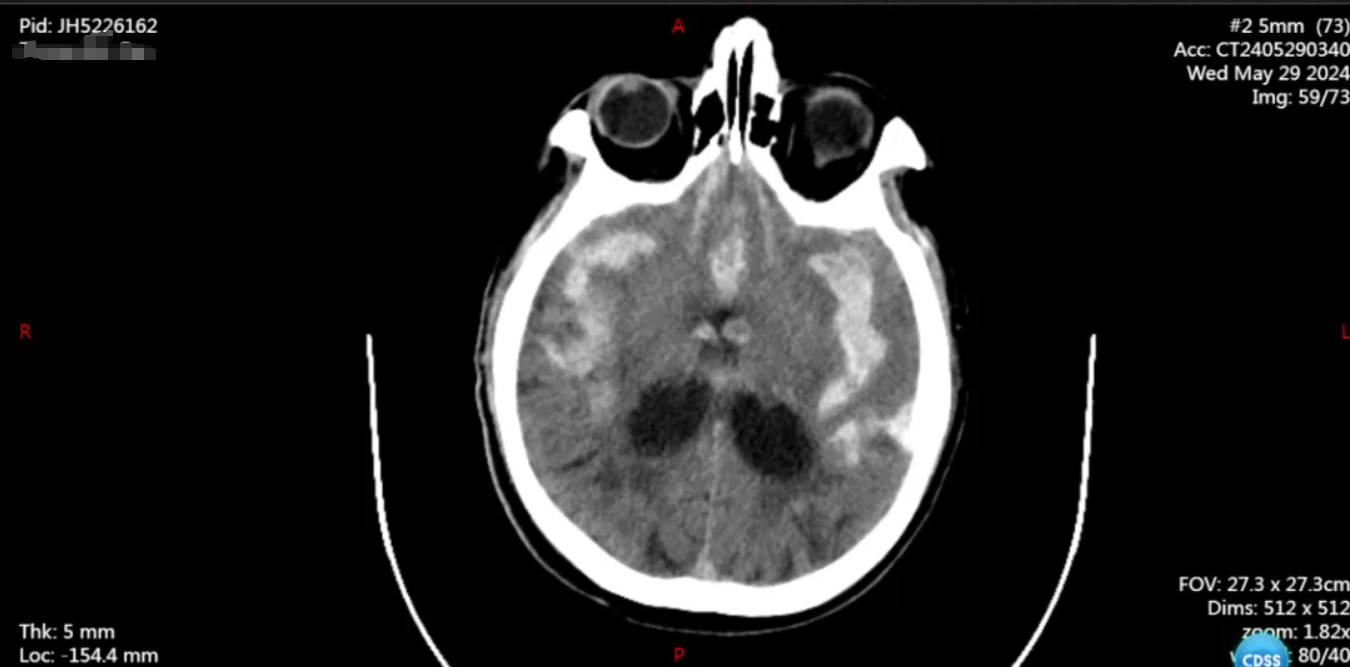

患者章爷爷(化姓),73 岁,安徽来安人,5 月 29 日晚上,因"被发现意识不清 2 小时"被送入外院就诊。接诊医生检查后发现他神志浅昏迷、无意识睁眼、不能言语、四肢肌力检查不配合等症状,做了头颅 CT 发现蛛网膜下腔出血。

患者病情危重,被紧急转院至我院,经头颈部 CTA 后,医生诊断:

1、左侧大脑中动脉瘤破裂伴蛛网膜下腔出血